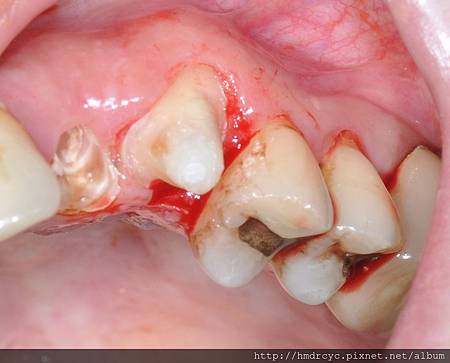

若是牙齒缺損太多

或者有某部分缺損嚴重

傷到牙周組織那就必須考慮鑄造鑄心

鑄造鑄心須先印模型製作

在模型上製作鑄心後

下一次療程才能在牙齒上裝上鑄心

製作完畢後裝入牙齒內 所以鑄心完成需兩次療程